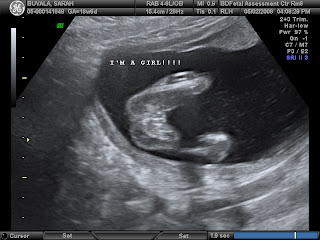

Today, 5/19/08, we had another ultra sound. We are at 21 weeks and she is still a she! We still have not decided on a name, but we are close. No, Mandy, it is not going to be Mandy (or anything close to that). :)

She was not nearly as active as she was last time, but livened up a little bit towards the end and had the ultra sound tech giggling.

Here are a few pictures from today's show!! (If you click on the pictures it will enlarge them for easier viewing. I didn't know that at first. Duh!)

Here are some pictures and a video from our second ultra sound... A girl! WOW!